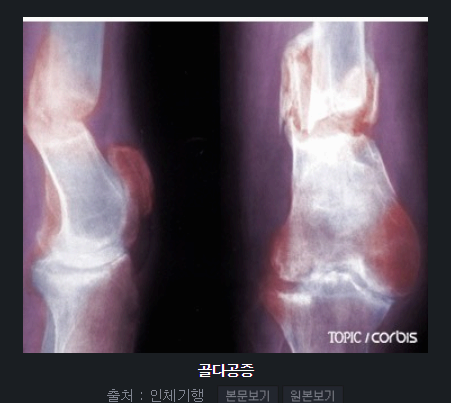

골다공증이란?

골다공증은 뼈가 약해지고 구멍이 숭숭 뚫린 것처럼 밀도가 낮아지는 질환이에요. 쉽게 말해 뼈가 부러지기 쉬운 상태가 되는 거죠. 주로 폐경 이후 여성, 고령층, 스테로이드 장기 복용자에게 잘 생깁니다.

문제는 골다공증이 있어도 특별한 통증이나 증상이 잘 안 나타난다는 거예요. 그러다 어느 날 작은 충격에도 손목이나 척추, 고관절 골절이 생기면서 발견되곤 합니다. 그래서 예방과 조기 치료가 정말 중요해요.